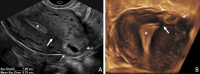

The Society of Radiologists in Ultrasound convened a multisociety panel to develop a first-trimester US lexicon based on scientific evidence, societal guidelines, and expert consensus that would be appropriate for imagers, clinicians, and patients. Through a modified Delphi process with consensus of at least 80%, agreement was reached for preferred terms, synonyms, and terms to avoid. An intrauterine pregnancy (IUP) is defined as a pregnancy implanted in a normal location within the uterus. In contrast, an ectopic pregnancy (EP) is any pregnancy implanted in an abnormal location, whether extrauterine or intrauterine, thus categorizing cesarean scar implantations as EPs. The term pregnancy of unknown location is used in the setting of a pregnant patient without evidence of a definite or probable IUP or EP at transvaginal US. Since cardiac development is a gradual process and cardiac chambers are not fully formed in the first trimester, the term cardiac activity is recommended in lieu of 'heart motion' or 'heartbeat.' The terms 'living' and 'viable' should also be avoided in the first trimester. 'Pregnancy failure' is replaced by early pregnancy loss (EPL). When paired with various modifiers, EPL is used to describe a pregnancy in the first trimester that may or will not progress, is in the process of expulsion, or has either incompletely or completely passed. © RSNA and Elsevier, 2024 Supplemental material is available for this article. This article is a simultaneous joint publication in Radiology and American Journal of Obstetrics & Gynecology. All rights reserved. The articles are identical except for minor stylistic and spelling differences in keeping with each journal's style. Either version may be used in citing this article. See also the editorial by Scoutt and Norton in this issue.